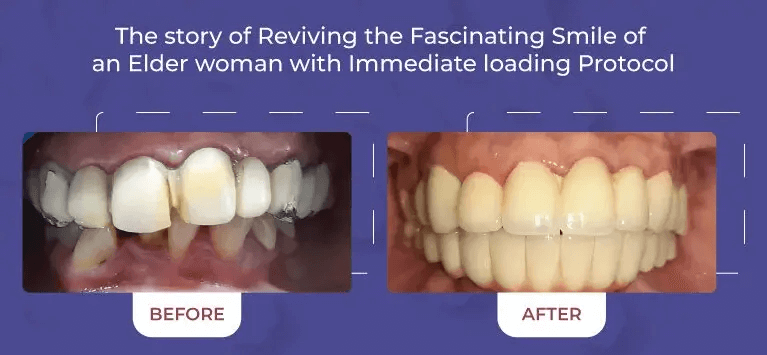

From routine cleanings and preventive care to advanced cosmetic and restorative dentistry, we offer a full range of dental services to keep your smile healthy and vibrant.

Creating Beautiful Smile

for All ages